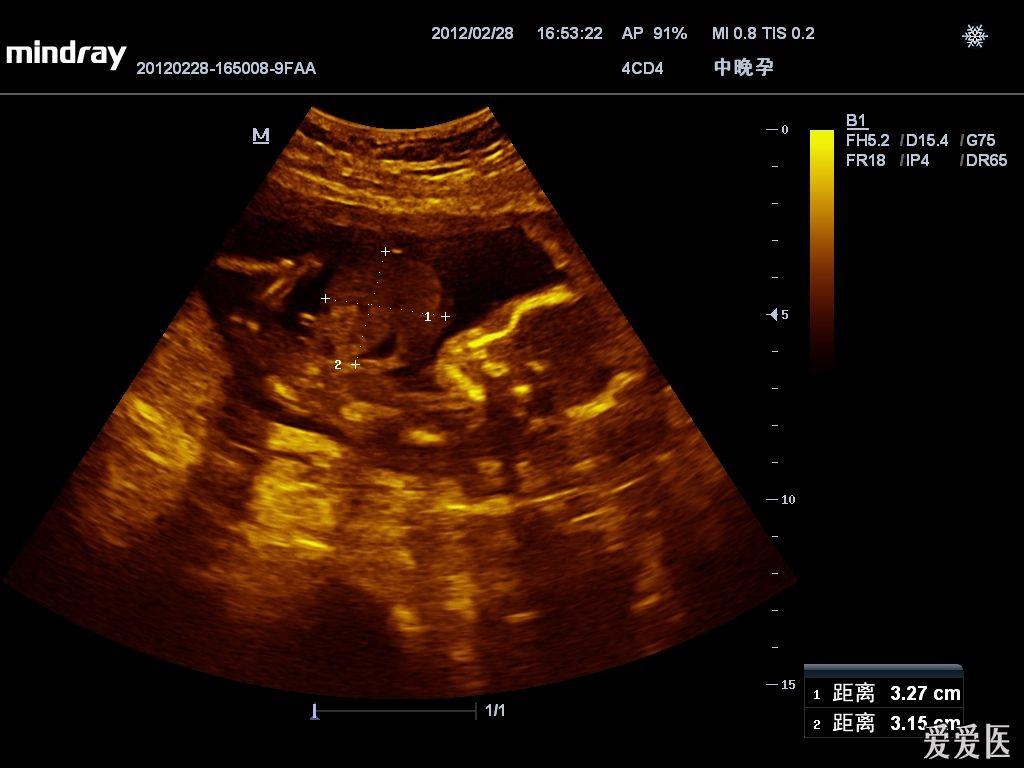

【读片】腹裂还是脐疝? - 超声医学讨论版 -丁香园论坛

图片尺寸720x576